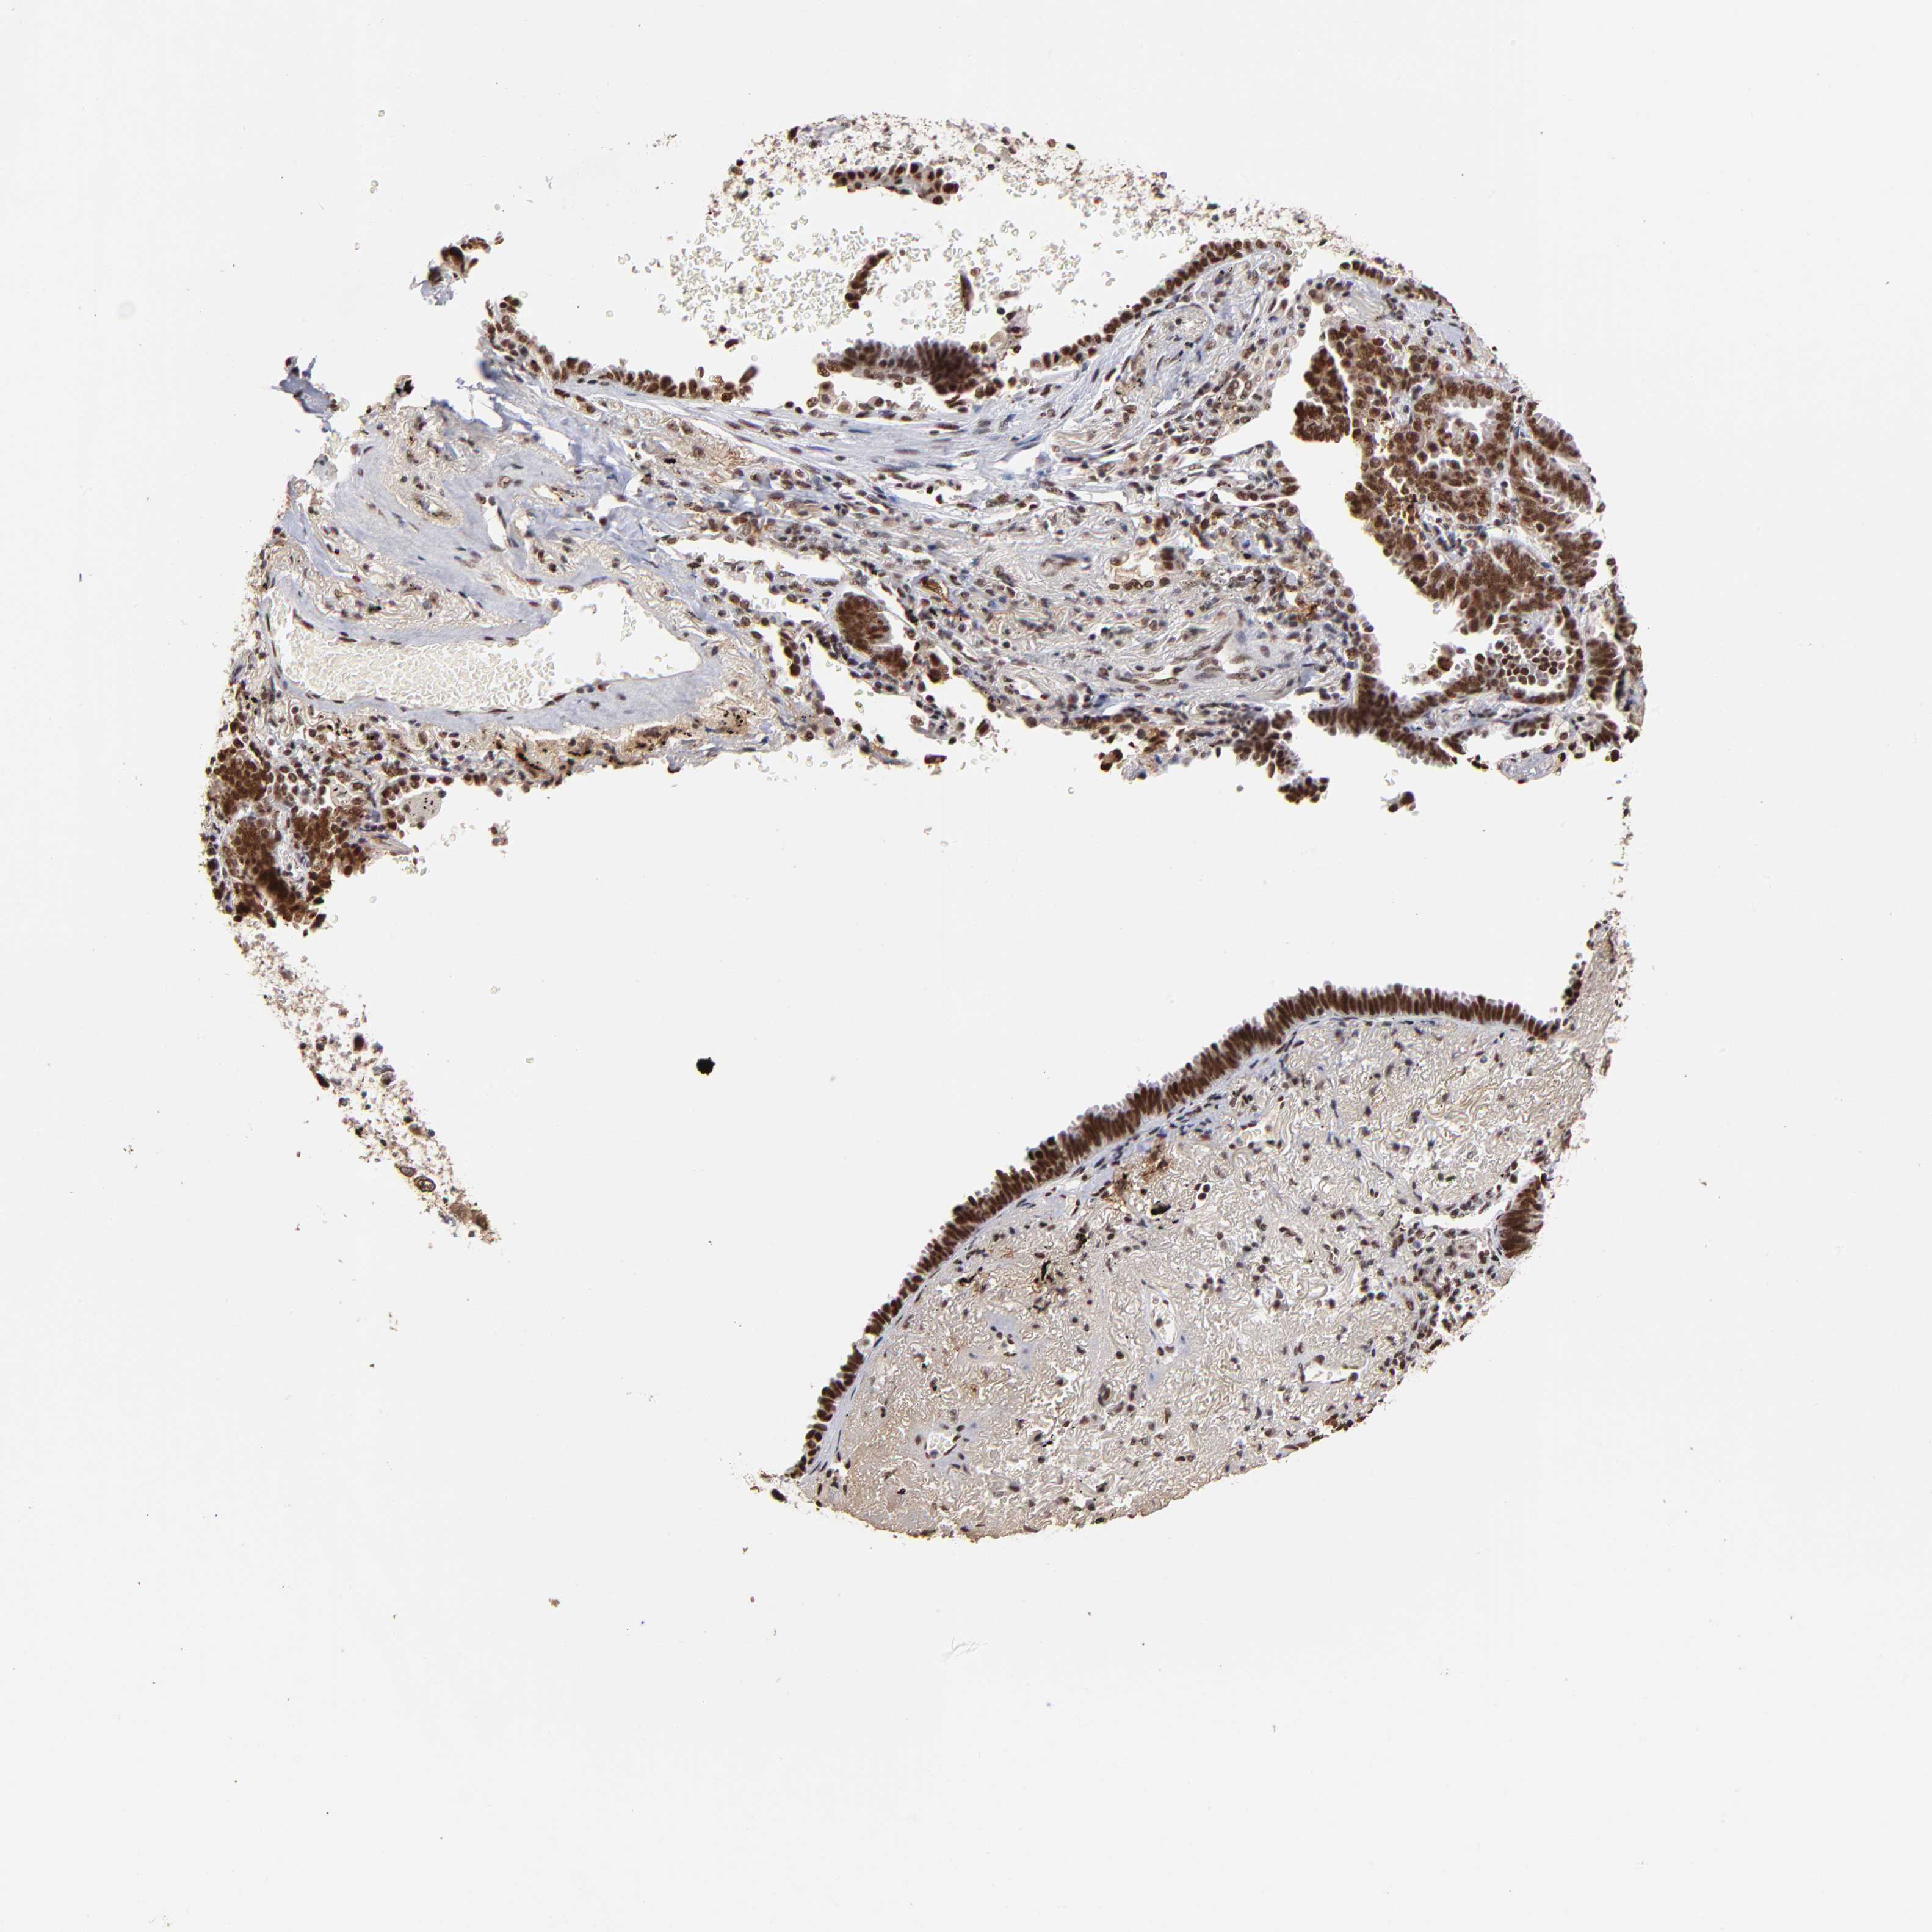

CANCER LUNG CANCER Show tissue menu